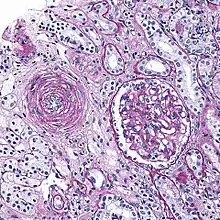

Micrograph showing hyaline arteriolosclerosis in the kidney. PAS stain.

Also arterial hyalinosis and arteriolar hyalinosis refers to thickening of the walls of arterioles by the deposits that appear as homogeneous pink hyaline material in routine staining.[3] It is a type of arteriolosclerosis, which refers to thickening of the arteriolar wall and is part of the aging process.[4]

It is often seen in the context of kidney pathology.[4]:284 In hypertension only the afferent arteriole is affected, while in diabetes mellitus, both the afferent and efferent arteriole are affected.

Lesions reflect leakage of plasma components across vascular endothelium and excessive extracellular matrix production by smooth muscle cells, usually secondary to hypertension.[7] Hyaline arteriolosclerosis is a major morphologic characteristic of benign nephrosclerosis, in which the arteriolar narrowing causes diffuse impairment of renal blood supply, with loss of nephrons.[5] The narrowing of the lumen can decrease renal blood flow and hence glomerular filtration rate leading to increased renin secretion and a perpetuating cycle with increasing blood pressure and decreasing kidney function.